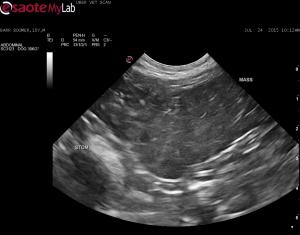

-u/s showed a well-encapsulated mass that was hyperechoic to the surrounding tissue with a course echotexture; it was impossible to determine if the mass was connected to the one noted subcutanously; no other abnormalities detected – no evidence of pancreatitis but this may be pressing on the pancreas causing the positive cPLI

– FNA’s and in house analysis compatible with a lipoma

Sonographically is this compatible with a lipoma? I guess an infiltrative lipoma or liposarcoma are also rule-outs.

This looks like lipoma and

This looks like lipoma and derives form the body wall and bordered by the peritoneum and the viscera moves separately.